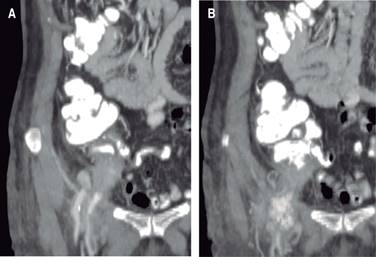

Mujer de 84 años, con antecedentes de hipertensión arterial sistémica y fibrilación auricular crónica en control con enalapril y verapamilo respectivamente. Dentro de su historial quirúrgico, cuatro años previo al padecimiento actual fue intervenida de urgencia por hernia inguinal directa estrangulada derecha, con contenido intestinal, abordada en región inguinal, requiriendo resección intestinal y entero-entero anastomosis término-terminal y hernioplastía Shouldice. Su postoperatorio satisfactorio, siendo egresada sin complicaciones. Su padecimiento actual inicia con masa en región inguinal, la cual crecía lentamente, presenta dolor inicialmente sordo, leve y no le da importancia; también crecimiento importante en las siguientes dos semanas, notando cambios de coloración, eritema y dolor importante, por lo que acude a hospital general donde se sospecha nuevamente hernia inguinal estrangulada. Se realiza ecografía en región inguinal, la cual reporta aparente hernia inguinal y abundante gas, avascular en la función Doppler. Deciden enviar a nuestra institución para su manejo. A la exploración se observa agitada, taquicárdica (105 latidos por minuto), moderadamente deshidratada; se explora masa rígida, eritematosa, aumento de calor local en región inguinal, la cual desplaza a cicatriz quirúrgica previa, muy doloroso a la palpación; presenta leucocitosis de 19,250 células/µl (neutrofilia 88.90%), aumento en tiempo de protrombina (Tp) y tiempo parcial de tromboplastina (TpT), el resto dentro de parámetros normales. Se sospecha hernia inguinal recidivante con contenido intestinal, aunque la apariencia de la masa recordaba a la apariencia de un absceso (Figura 1). Se decide su paso a quirófano, bajo anestesia regional se realizó acceso por cicatriz previa, encontrando absceso importante aproximadamente 400 cm3 que se drena en su totalidad, se observa plastía inguinal previa intacta, no se observan sacos herniarios, no se observa tampoco un evidente origen de material purulento, no se puede determinar claramente el origen del absceso. Se decide manejo de herida abierta para cierre por segunda intención y continuar estudiando a la paciente. Se realizan curaciones a necesidad del gasto y se realiza horas después una tomografía contrastada abdominal a determinar sitios probables de origen del absceso, se sospecha en enfermedad diverticular complicada. El reporte por el servicio de imagen determina apéndice vermiforme edematoso, el cual sale aparentemente por el conducto femoral y una colección pequeña periapendicular (Figura 2). Se programa nueva laparotomía exploradora encontrando múltiples adherencias alrededor del sitio de anastomosis realizada hace cuatro años, las cuales se liberan alcanzando ciego y apéndice vermiforme (Figura 3). Se realiza apendicectomía con manejo del muñón Pouchet, al extraer la pieza quirúrgica se encuentra la punta totalmente perforada; el cierre del defecto herniario se hizo con dos puntos simples de polipropileno 00, se decide no colocar malla por el alto riesgo de infección. El postoperatorio fue satisfactorio, con disminución de leucocitosis a 9.43 células/µl y normalización de Tp y TpT, con una estancia total de seis días, la herida inguinal granuló por segunda intención, continuando con curaciones y supervisión semanal hasta lograr cierre. El reporte histopatológico final menciona apéndice cecal con infiltración leucocitaria en mayor cantidad en su mitad distal, hipertrofia linfoide en su mitad proximal, punta perforada y negativo a malignidad (Figura 4).

Figura 2: Imágenes tomográficas del apéndice cecal a través de canal femoral (A) y cubriendo con contraste canal femoral y colección residual (B).